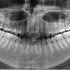

Höchste Bildqualität

X-ERA SMART verfügt über ein einzigartiges Patientenpositionierungssystem im 3D Bereich, das jede Bildverzerrung durch Patientenbewegung komplett ausschließt. Das Technologiekonzept erzeugt eine Bildqualität in extrem hoher Auflösung. Zwei verschiedene Aufnahmegrößen mit einer Voxel Größe von 80μm / 100 μm liefern in jeder Sichtfeldgröße (FoV) exzellente Ergebnisse für die weitere Diagnostik und Behandlung.

Nacholgend ein paar phänomenale Bilder & Werte,

die nicht nur einem Fachmann die Sprache verschlagen:

Aufnahmeparameter: Ceph LA; 82 kV; 10 mA; 8.0 s; 0.8 mm CU + 6.0 mm AL

gemessene Dosis: 2.99 µGy